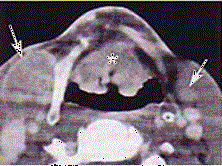

问题 男,60岁,因吞咽疼痛伴咽异物感一个月就诊。间接喉镜下检查发现会厌侧面轻度糜烂、不光滑、隆起,既往有吸烟史。 CT检查见下图,进一步的检查是 ( )

选项 A、放疗 B、活检送病理 C、密切观察 D、抗生素治疗 E、纤维喉镜检查以明确病变范围

答案 B